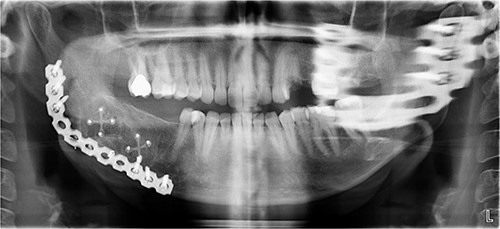

A 40-year-old woman presented with swelling on the right side of her mandible. She had completed orthodontic treatment 2 years earlier. A panoramic radiograph showed a unilocular radiolucency extending from the mandibular angle to the right first molar region (Figs 1–3).

Panoramic radiograph showing a unilocular radiolucency extending from the right mandibular angle to the right first molar region.

Panoramic radiograph highlighting the extent of the lesion from the mandibular angle to tooth #46.